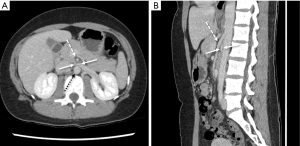

Cross-sectional imaging with CT and MRI relies on vessel diameter and, to a lesser extent, SMA angle to identify pathologic narrowing of the LRV. A normal aorta-to-SMA angle is between 45 and 90 degrees. An angle of 35 degrees in sagittal dimension suggests NCS (37) (Figure 5A). In the axial plane, a characteristic “beak” sign with abrupt narrowing of the LRV at the SMA is reported to have a sensitivity of 91.7% and specificity of 88.9% (38). As normal absolute values vary by patient, studies have focused on the ratio of diameters of the LRV at the renal hilum as compared to those at the narrowed AM segment. On CT, a hilar-to-AM diameter ratio of ≥4.9 has a 66.7% sensitivity and 100% specificity for NCS (Figure 5B) (2). A separate study demonstrated a 91% sensitivity and 91% specificity for NCS with a “compression ratio” of 2.25, which was described as adequate to raise suspicion for the disease, in the context of symptoms (39). Predictably, higher compression ratios were associated with more symptoms.